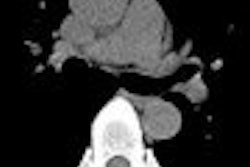

| Researchers found that more than 86% of pleural plaques were completely flat and 91% were symmetrical. Eleven percent of patients had diffuse pleural thickening (top). Plaques that were asymmetrical in shape and mass-like were considered suspicious for malignancy (above). Plaques were detected in the lung fissures, mediastinum, diaphragm, and costal regions (below). All images courtesy of Dr. Heidi Roberts. |

The results showed that 308 (73%) patients had pleural plaques. At least 83% of the plaques had at least some calcification, ranging from "tiny spots" at CT to complete calcification in 11%. Most involved the costal (more than 97% of plaques) and diaphragmatic (more than 88% of plaques) pleura.

In all, 86% of the plaques were flat and 91% were symmetrical. More than 80% of pleural plaques "were completely flattened and inconspicuous, while 10% had these lobulated and rather thick nodules," Roberts noted.

Conversely, 14% of plaques were lobulated, 2% were asymmetric with a right-sided dominance, and 1% were associated with pleural effusions. Eleven percent of patients had diffuse pleural thickening.